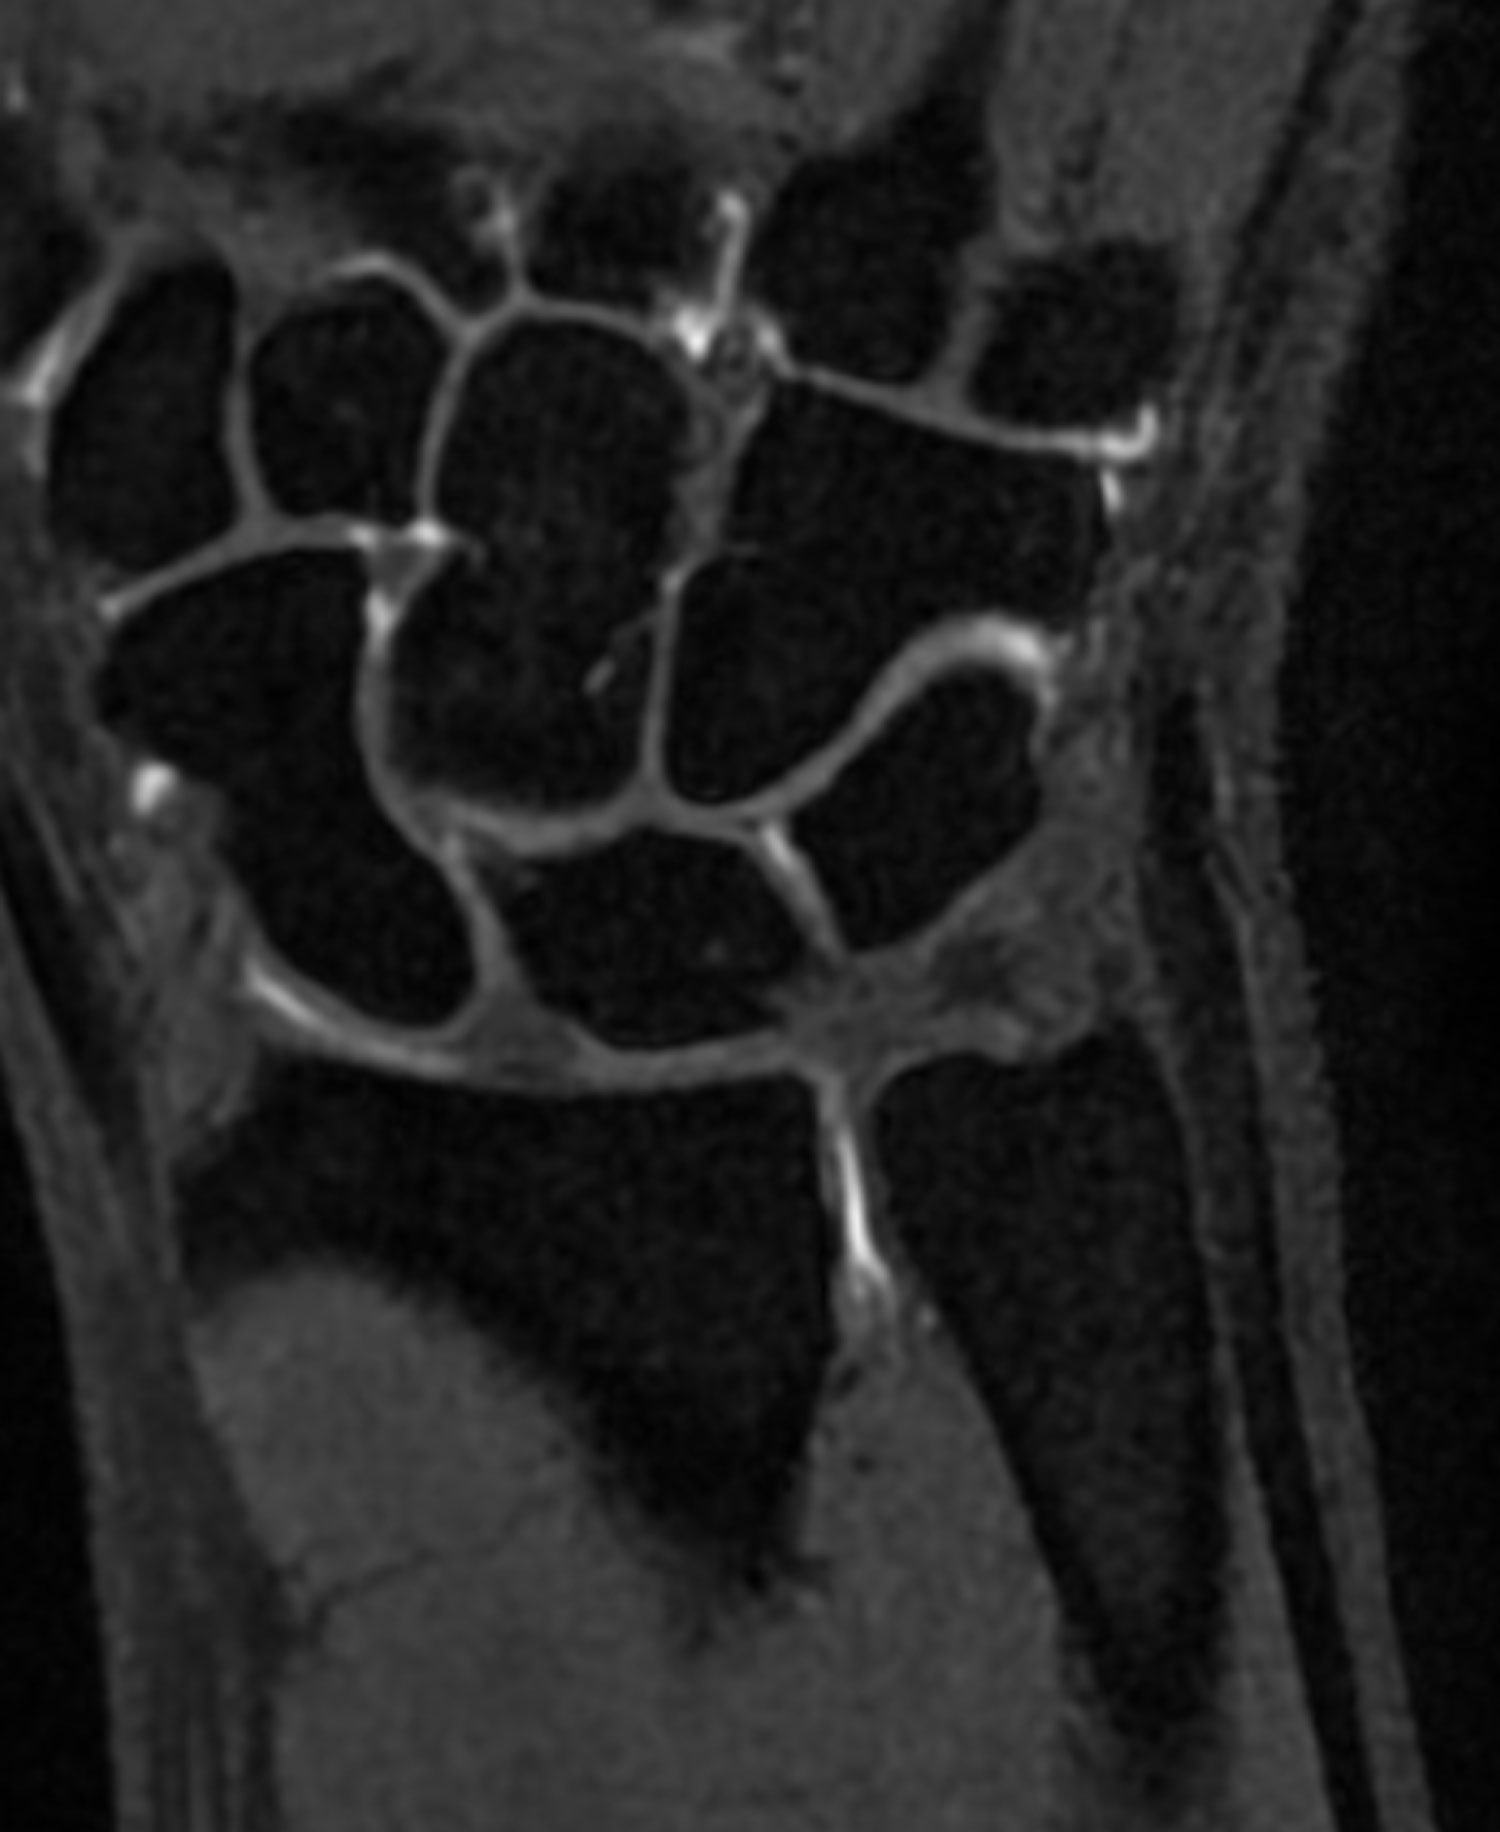

Die Magnetresonanztomographie (MRT) mit rheumaspezifischer Abklärung ist eine medizinische Bildgebungstechnik, die sich auf die genaue Untersuchung von Gelenken, Muskeln und Weichgeweben bei Patient:innen mit Verdacht auf Rheuma spezialisiert hat. Entzündliche Prozesse können auf dieser Grundlage ebenso frühzeitig erkannt werden, wie z.B. verschiedene Formen von Rheuma wie rheumatoide Arthritis, Spondyloarthritis und Psoriasisarthritis.

Während der MRT-Untersuchung werden hochauflösende Bilder der betroffenen Gelenke und des umliegenden Gewebes erstellt. Dies ermöglicht eine genaue Beurteilung von Entzündungen, Schwellungen, Gelenkerosionen, Knorpelschäden und anderen strukturellen Veränderungen, die bei rheumatischen Erkrankungen auftreten können. Die MRT kann auch Informationen über den Verlauf der Krankheit liefern und helfen, die richtige Behandlungsstrategie zu entwickeln.